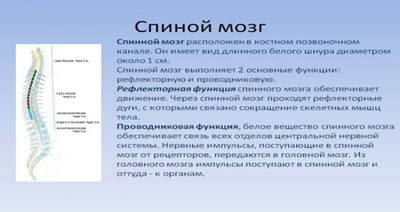

Спинной мозг и двигательная активность: Важные аспекты